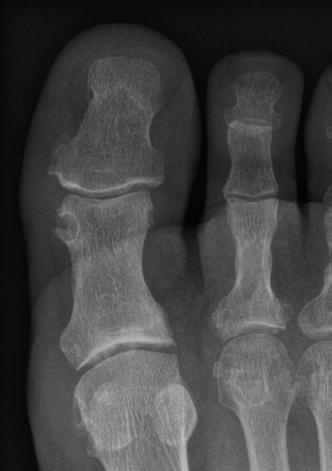

Die Gicht ist chronisch, wenn sich über längere Zeit zwei oder mehr Gichtanfälle pro Jahr ereignen oder die Gelenkentzündungen vor sich hinschwelen, ohne Anfälle zu produzieren. Eine chronische Gicht kann Gelenke verformen und Knochen und Gelenkknorpel zerstören. So geht die Gicht im Grosszehengrundgelenk häufig mit dessen Schiefstellung einher, einem Hallux valgus. Die Betroffenen sind in ihrer Beweglichkeit eingeschränkt und empfinden Schmerzen bei Bewegung und Belastung.

Während die akute Gicht (links) in die Augen fällt, braucht es ein Röntgenbild, um die zerstörerische Wirkung einer chronischen Gicht zu sehen.

Bildgebende Verfahren kommen nur zum Zuge, wenn die Laboruntersuchungen Zweifel aufkommen lassen. So können Röntgenbilder den Abbau von Knochen- und Knorpelmasse zeigen. Das sind meistens schon Langzeitschäden nach mehrmaligen Gichtanfällen. Gichtknötchen (Tophi) und Ablagerungen von Uratkristallen auf der Knorpeloberfläche lassen sich im Ultraschall oder in der sogenannten Dual-EnergyComputertomographie (DECT) erkennen.